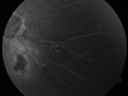

Pigmented Choroidal Mass Right Eye - Melanoma vs. Nevus vs. Unilateral Melanocytic Proliferation - 4 Month Follow-Up Images692 views71-year-old man his vision 4 month follow-up. Vision is 20/60 and patient sees flashing lights. Lesion has grown slightly in the superior half of the macula.     (0 votes)

PHOTOGRAPHS: Photos confirm clinical findings.

FLUORESCEIN ANGIOGRAPHY: The right eye shows hyperfluorescence corresponding to a window defect overlying the nevus. The choroidal vasculature can be easily seen throughout the area in a dependent fashion, suggestive of chronic subretinal fluid. There is also hyperfluorescence inferior to the optic nerve with hypofluorescence over the area of geographic atrophy. There is some stippled hyperfluorescence within the lesion in the late frame. The hyperfluorescence in general fades in the late frames. There is no evidence of any active leakage. The drusen over the surface of the nevus inferonasal to the optic nerve, which is overall dark, do stain in the late frames as well. The left eye is angiographically normal throughout the studies.